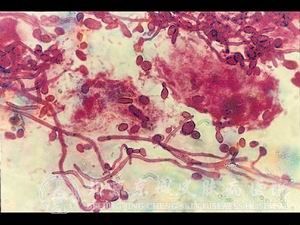

念珠菌病的检查有哪些,北京京城皮肤医院指出,念珠菌病是皮肤病中的一种常见的疾病。由于各种念珠菌的不同,各种念珠菌病的症状表现也是基本不同的。因此,很多的病人都不是非常了解念珠菌病的检查有哪些。为了帮助广大患者更加了解念珠菌病的检查有哪些,北京京城皮肤医院将为您详细介绍念珠菌病的检查有哪些。

北京京城皮肤医院指出, 根据患者的发病阶段,我们做出相应的组织病理,发现皮肤炎,肺炎,化脓性皮肤,肉芽肿皮肤等都会有菌丝存在。但是组织病理时,需要与曲菌、毛霉、蛙粪霉想区分。